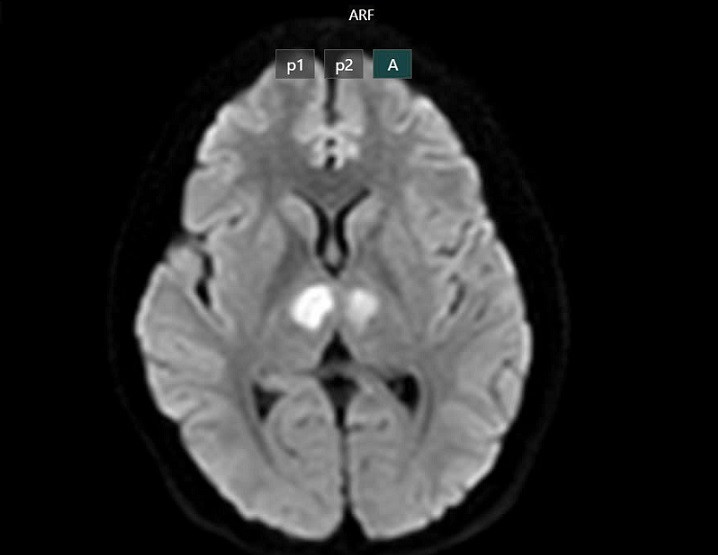

Gia đình phát hiện ra bệnh nhân bất tỉnh, gọi hỏi không đáp ứng nên đã đưa đến bệnh viện gần nhà cấp cứu. Kết quả chụp MRI cho thấy não bệnh nhân có hình ảnh tổn thương vùng đồi thị hai bên. Gia đình xin chuyển bệnh nhân sang Bệnh viện Bạch Mai để tiếp tục điều trị.